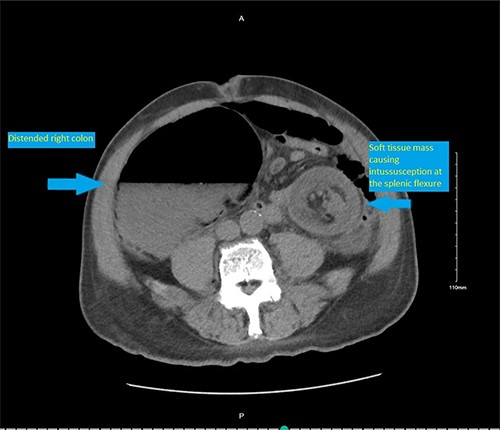

On presentation, the patient was afebrile with stable vital signs. Physical exam was significant for a markedly distended abdomen with generalized tenderness, worse on the left side with resonance on percussion. There were no abdominal hernias. The digital rectal examination revealed no lesions. The rectal tone was good and there was no stool in the vault. Laboratory evaluation showed hypokalemia (3 mmol/L) and mild anemia (hemoglobin 13.1 g/dl).A computed tomography (CT) scan of abdomen and pelvis was performed and showed colonic intussusception in the descending colon with a possible lipoma/ fat containing lesion associated with the wall of the distal left colon and proximal sigmoid colon measuring 4.2 cm × 4.3 cm (Figs 1–3). There was marked distended right colon and transverse colon but no sign of bowel perforation or free air seen. There is mucosal thickening of the left colon with pericolic stranding. Developing ischemia of the left colon could not be ruled out. With the findings on imaging, it was determined that the patient would undergo an exploratory laparotomy with left hemicolectomy to remove the intussuscepted bowel.

CT scan pelvis (axial cut) showing a soft tissue lesion in the left colon, with surrounding fat stranding and distended right colon.

CT scan pelvis (axial and coronal cuts) showing a soft tissue lesion in the left colon, with surrounding fat stranding and distended right and transverse colon.